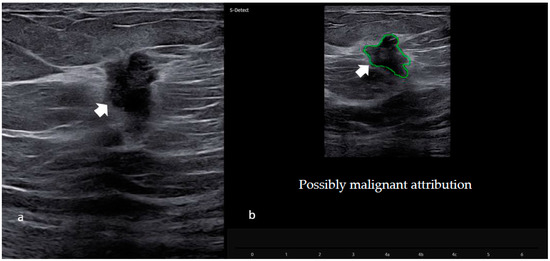

S-detect CAD information (Computer Aided Diagnosis of the Samsung RSV80 or 85 machine, Samsung Medison Co., Ltd., Seoul, Republic of Korea) was available for a subgroup of patients (209). S-Detect (a CAD based on a deep-learning algorithm to evaluate ultrasound breast lesions) was used to obtain a categorization of the breast lesion as either “possibly benign” or “possibly malignant.” For each lesion, the radiologist, after the acquisition of both longitudinal and transverse B mode images, placed a mark in the center of the lesion: the system automatically provided a region-of-interest (ROI) around the border of the mass with a “possibly benign or malignant” score, as shown in Figure 2.

Figure 2. CAD software evaluation (S-detect) in the US images. (a) Ultrasound image of the suspicious hypoechogenic nodule with irregular margins in the right breast (as shown by the arrow). (b) Region-of-interest (ROI) of the same breast lesion after the S-Detect evaluation. Histological examination of the biopsy confirmed the presence of a malignant neoplasm (invasive ductal carcinoma).